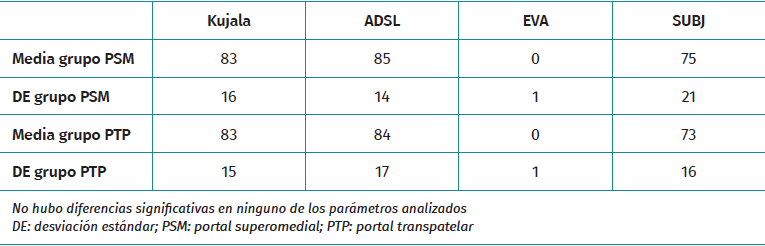

Se realizaron evaluaciones clínicas mediante cuestionarios clínicos para evaluar el dolor y la pérdida de función a una media de 5 años en ambos grupos. La pérdida de función se evaluó mediante los cuestionarios Kujala y ADLS(12,13). Para evaluar el dolor, utilizamos la escala visual analógica (EVA) y el dolor rotuliano medido mediante una escala subjetiva que oscila entre 0 si el paciente siente un dolor insoportable y 100 si no siente dolor alguno(14,15).

No hubo diferencias significativas entre los grupos PTP y PSM en términos de dolor o pérdida de función a los 5 años. La puntuación de Kujala para los pacientes del grupo PTP fue de 83,15 y para los pacientes del grupo PSM fue de 83,16 (p = 0,69). Del mismo modo, la puntuación ADLS fue de 84,17 para los pacientes PTP y 85,14 para los pacientes PSM (p = 0,82). Además, la EVA mostró una media de 0 en los grupos PTP y PSM, con una p= =0,3396. La escala SUBJ fue de 75 para los pacientes PTP y de 73 para los pacientes PSM, con p = 0,566 (Tabla 3).